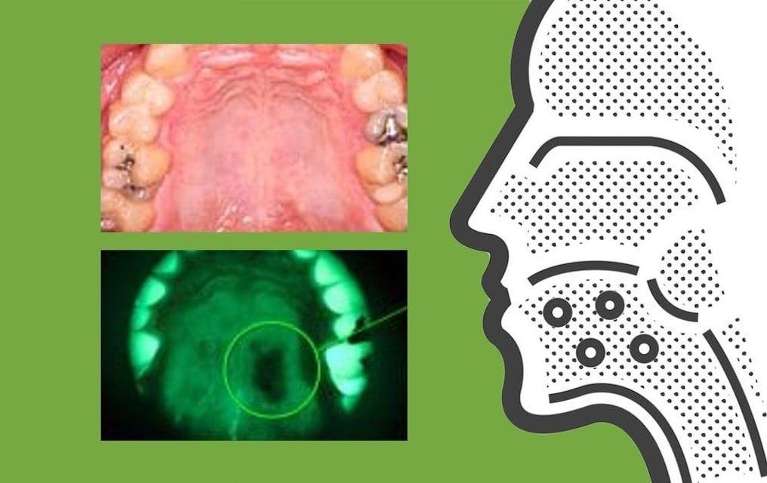

VELscope is an oral cancer screening system that utilizes fluorescence visualization. Fluorescence visualization helps your dentist detect potentially cancerous lesions and other lesions that might not be apparent to the naked eye. The FDA and Health Canada cleared the VELscope for cancer detection, and it is also cleared to help surgeons determine appropriate surgical margins.

VELscope emits specific wavelengths of blue spectrum light. The blue light disrupts fluorophores, which are naturally occurring molecules that absorb specific wavelengths of light, causing them to emit different light in identifiable shades of red, yellow, and green.

Normal fluorescence patterns tend to make oral tissue appear green under blue light, while abnormal fluorescence patterns may make oral tissue look darker or brighter. VELscope’s filter makes fluorescence visualization possible by enhancing the contrast between normal and abnormal tissue by blocking reflected blue light.